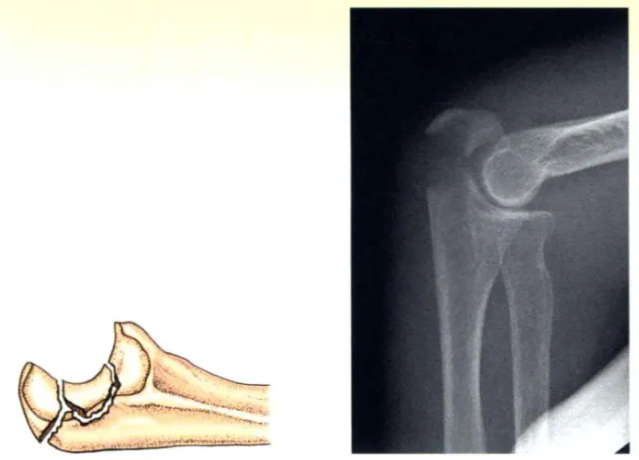

B型:橫(heng)形(xing)壓縮骨(gu)折

B型:關(guan)節(jie)面(mian)的(de)壓縮必須(xu)識(shi)別、復位,并使用植骨和(he)/或內植物來穩(wen)定(ding);骨折(zhe)固定(ding)方(fang)式如A型